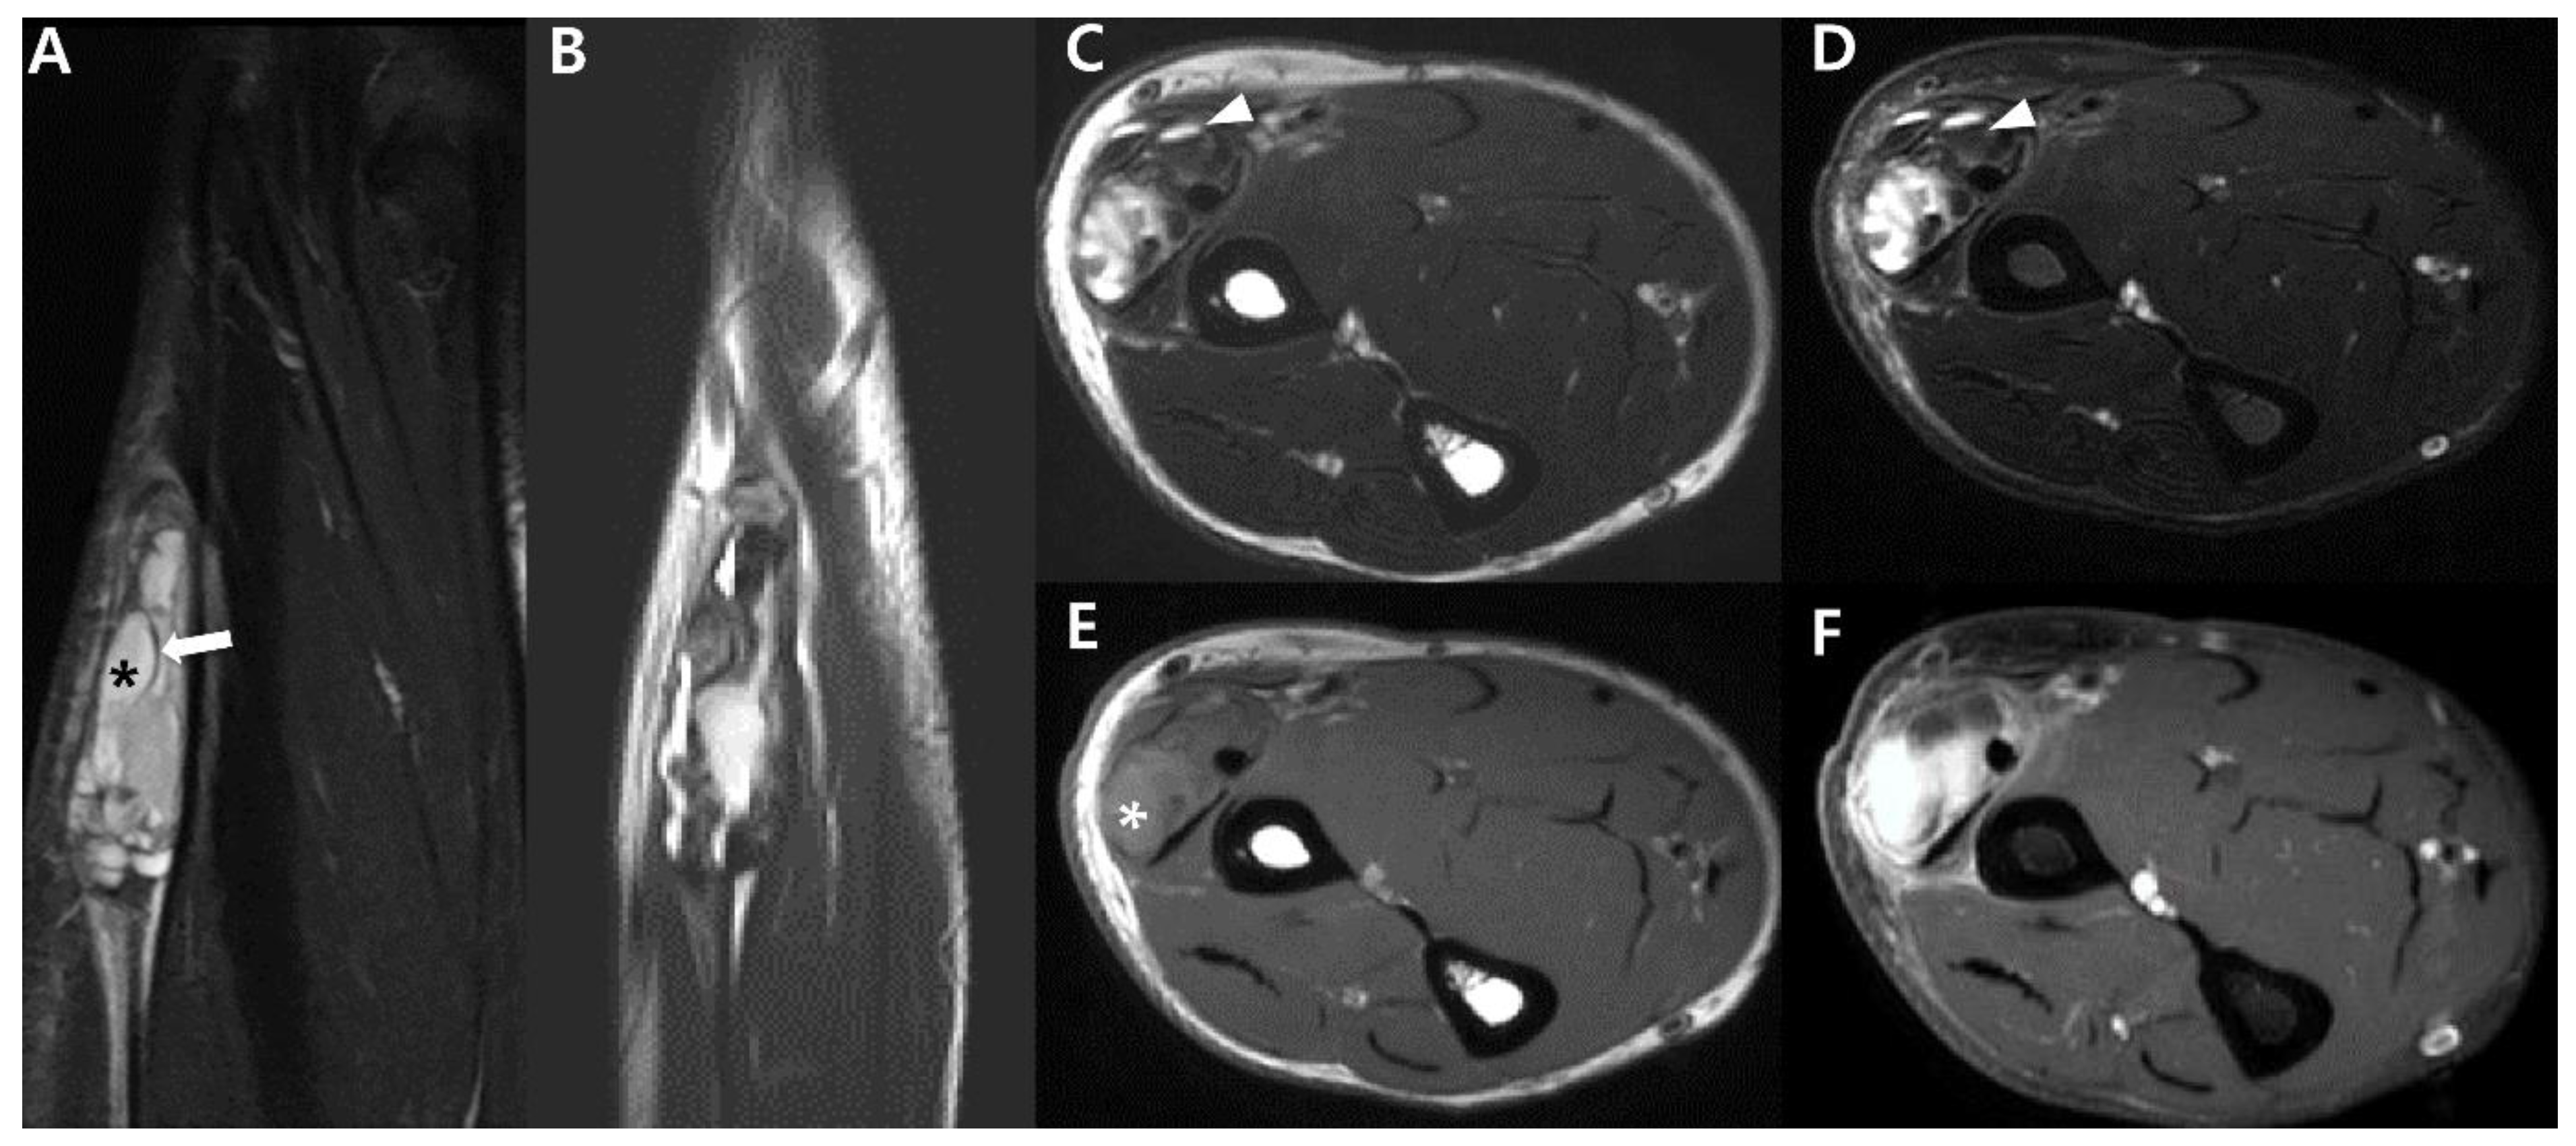

2.4. Magnetic Resonance Imaging (MRI)

2.5. Advanced MRI

3. Uncommon Primary Sites of Synovial Sarcoma in the Extremities

- Nakanishi, H.; Araki, N.; Sawai, Y.; Kudawara, I.; Mano, M.; Ishiguro, S.; Ueda, T.; Yoshikawa, H. Cystic synovial sarcomas: Imaging features with clinical and histopathologic correlation. Skelet. Radiol. 2003, 32, 701–707. [Google Scholar] [CrossRef] [PubMed]